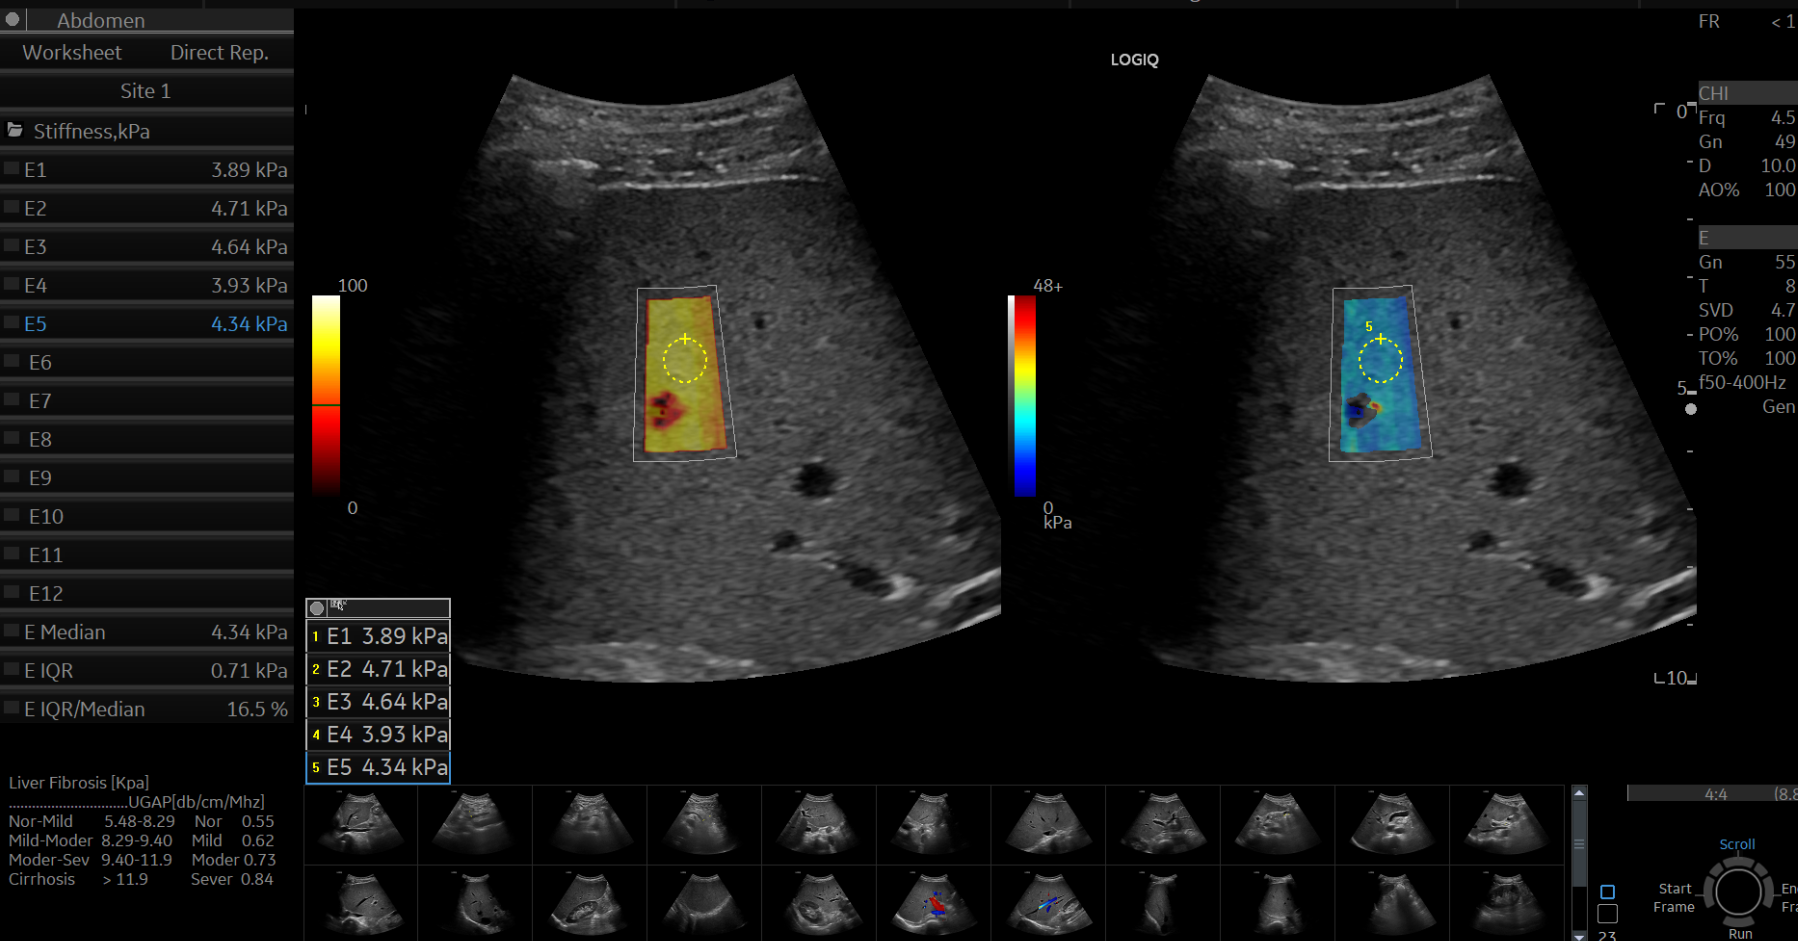

간초음파 B-mode 영상에서 거친 에코음영과 간 하연 둔화(inferior hepatic angle blunting)를 보여 전형적인 만성 간질환을 시사하고 있지만, 탄성초음파 상 탄성계수는 평균 4.3 kPa로 정상범주였으며, UGAP 정량분석에선 평균 0.58 dB/cm/MHz로 마찬가지로 정상범주 내였습니다.

탄성초음파나 UGAP 정량분석에서 정상수치를 보였다는 것이 미만성 간질환의 가능성을 배제할 수 없다는 사실을 극명하게 보여준 임상사례였습니다. 여담이지만, 만성 간질환 중에서도 알콜성 간질환의 경우 탄성계수가 다른 원인에 의한 경우보다 높다는 보고가 있는데, 이번 사례는 그러한 보고와 정반대의 결과를 보여주고 있다는 점도 특이했던 것 같습니다.

결론적으로, 탄성초음파는 탄성계수가 높을 경우에는 유의미한 간섬유화나 간내 염증의 증거가 될 수 있으나, 탄성계수가 정상범주 안 이라도 B모드 영상에서 의미있는 소견들이 존재한다면 반드시 만성 간질환의 가능성을 배제하지 말아야 합니다.